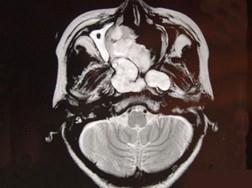

女性,41岁,鼻腔流脓涕3年,鼻部面部肿胀1年,近来加重,MRI检查如图,请选择最可能诊断 ( )